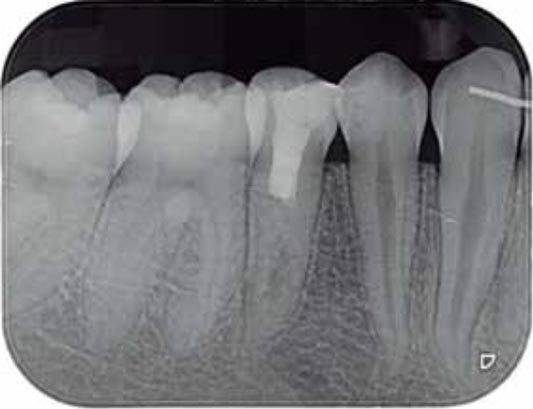

Imágenes:

Radiografía previa y final del tratamiento.

Medimos el ápice, retiramos el relleno anterior y colocamos relleno biocompatible.